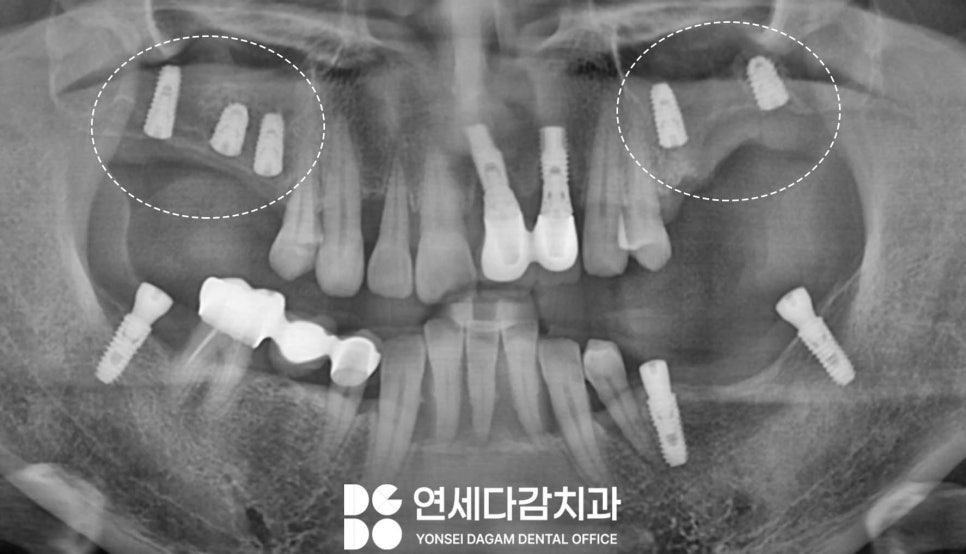

가락동 치과 에서 예를 들자면

앞니가 많이 흔들리고

뼈 상태가 좋지 않거나,

위턱뼈가 얇아져 별도의 뼈이식술 같은

시술 동반이 필요한 경우가 있습니다.

특히 위턱 어금니 부위는

골밀도가 낮고

저작 시 힘이 많이 받는

부위이기 때문에 임플란트 실패율이

높게 나타나는 곳입니다.

골 높이가 낮은 경우에는 상악동이라는

점막에 손상을 줄 수 있기 때문에,

점막을 위로 거상하여

공간을 확보하고 골이식을 시행한 뒤

고정체를 식립하는 단계적 접근이 필요합니다.

아래 앞니 부위 역시

뼈 상태가 좋지 않아

안정적으로 결합할 수 있는

타입을 선택하여

고정력을 확보합니다.

이 과정을 통해 수술 부위 모두

골 유착이 원활하게 진행되어

안정적인 결과를 얻을 수 있게 됩니다.